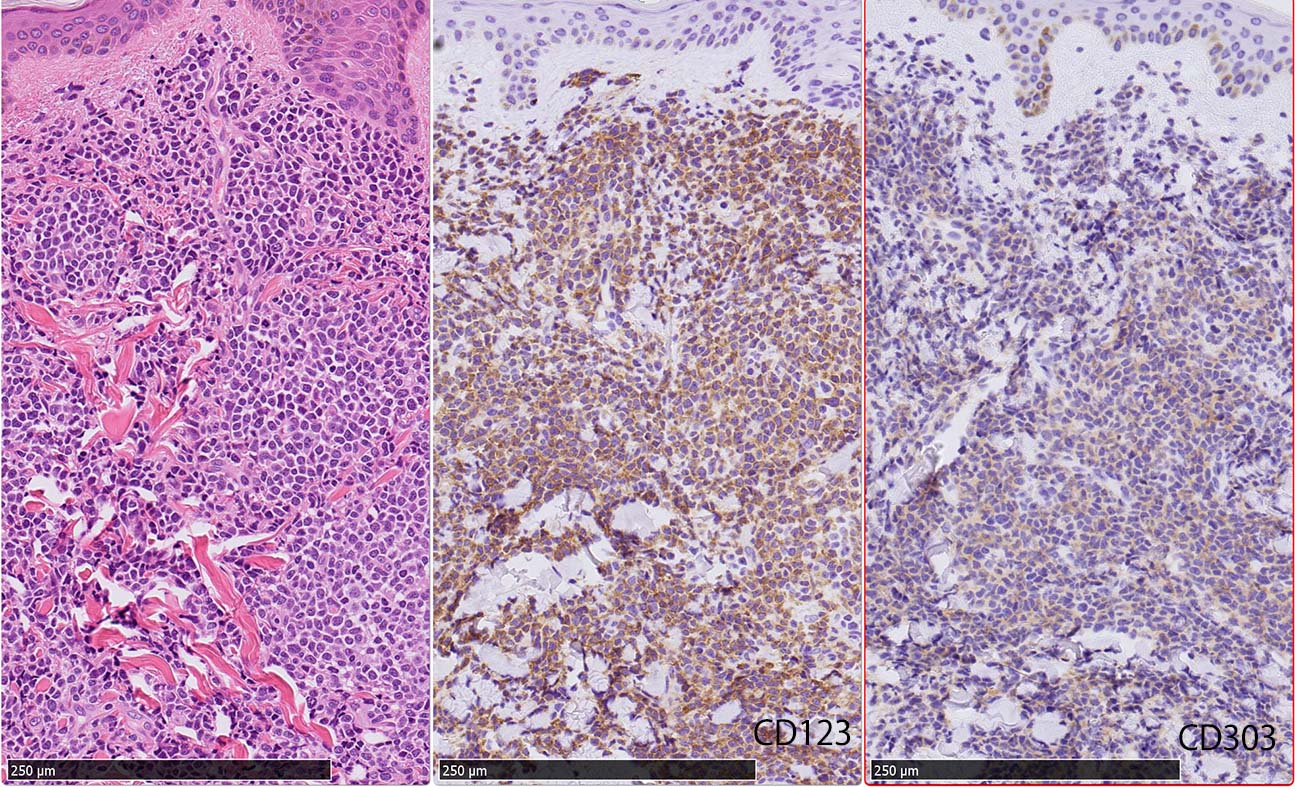

皮膚病変

IWT-case: 4つの点で囲んだ紅斑から生検.

皮膚病変は64-100%の症例で認められ皮膚病変が契機となり診断されることも多い.

マクロ所見は多彩で, 孤在性から播種性の分布を呈し, 腫瘤, 局面, 紅斑いずれの形態もとりえる.

腫瘍細胞は真皮を主座として, 皮下脂肪織まで, びまん性かつ単調monotonousに増殖することが多く, 表皮向性はみられない. 本例では血管や付属器中心あるいは脂肪織内に結節状の浸潤増殖を示した.

本例皮膚真皮増殖細胞はCD4+, CD56+, CD123+, CD303+, lysozyme(-). がん研有明病院, Sakamoto K, Takeuchi K先生にconsultationを行い, TCF4, TCL1の陽性が確認された.(consultationを受けていただいた両先生に深謝いたします.)

BDCA-2(CD303)